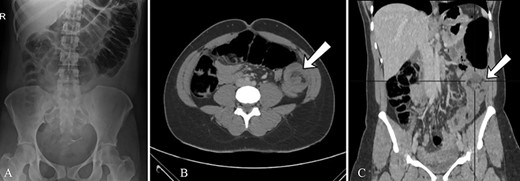

Radiological findings, (A)AXR, gaseous distention of the colon as far as mid-descending colon (B) CT, large bowel obstruction with transient point in the mid-descending colon secondary to large bowel intussusception.

Erect chest and abdominal X-ray was performed which showed gaseous distension of the colon as far as the mid-descending colon with very little gas distal to this (Fig. 1A). Consequently a computed tomography (CT) scan of her abdomen and pelvis was obtained which confirmed the plain X-ray findings and showed gaseous distension of the transverse colon with a transition point in the mid-descending colon where a colo-colic intussusception was demonstrated due to a large descending colon lipoma. The distal colon beyond the intussusception was completely collapsed (Fig. 1B).